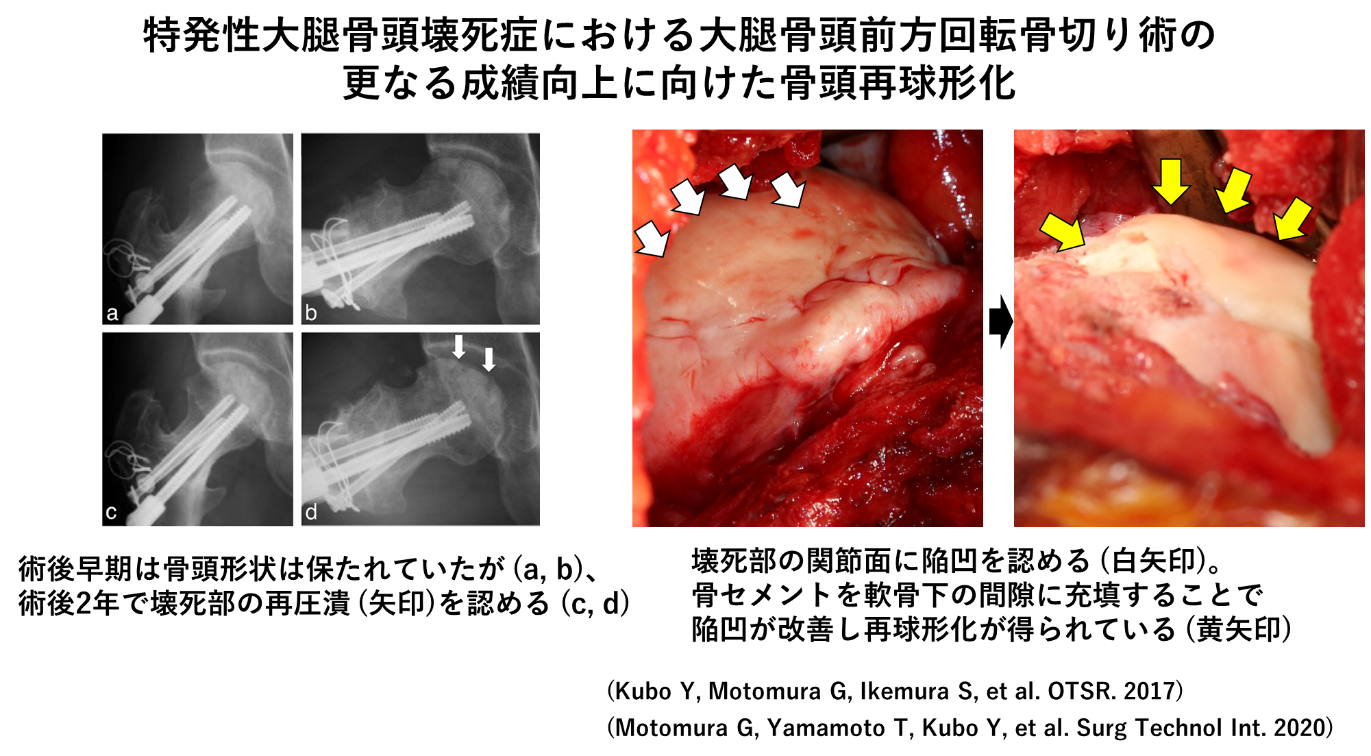

杉岡洋一先生が開発された大腿骨頭回転骨切り術は、現在では大腿骨頭壊死症のほか若年性の大腿骨頭軟骨下脆弱性骨折症例にも適応し、良好な成績を報告しています。近年、大腿骨頭前方回転骨切り術では前方に回転移動させた壊死域が術後再圧潰するか否かが、術後成績に影響を及ぼすことが明らかとなりました。そこで前方回転骨切り術の際、圧潰幅の大きい症例では圧潰部の間隙に骨セメントを充填する再球形化を併用しています。さらに3Dシミュレーションモデルの利用により、術前計画は精密に行えるようになりましたが、今後はいかにして計画通りに手術を行えるかを突き詰めていきたいと考えています。